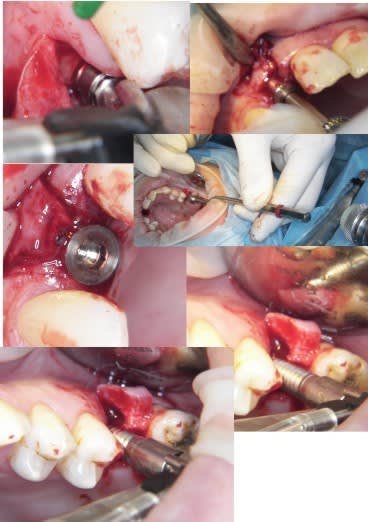

j'ai fait une bonne matinée implanto ce matin avec mélange des techniques 2 Summers avec un mélange expanseurs/condenseurs Meissinger, ostéotomes impactés pour la corticale qui faisait de la résistance, eponge pour la membrane, puis une reprise d'echec sur une mise en vitrine immédiate (fracture en mangeant une frite calcinée, à un mois!le 14/07)déposé le 15/07 mais avec mouvements pendant 24 heure et de 3.4mm j'ai du passer à 5.2!

les photos d'hier avec la mise en vitrine immediate et la reprise

--

xbk